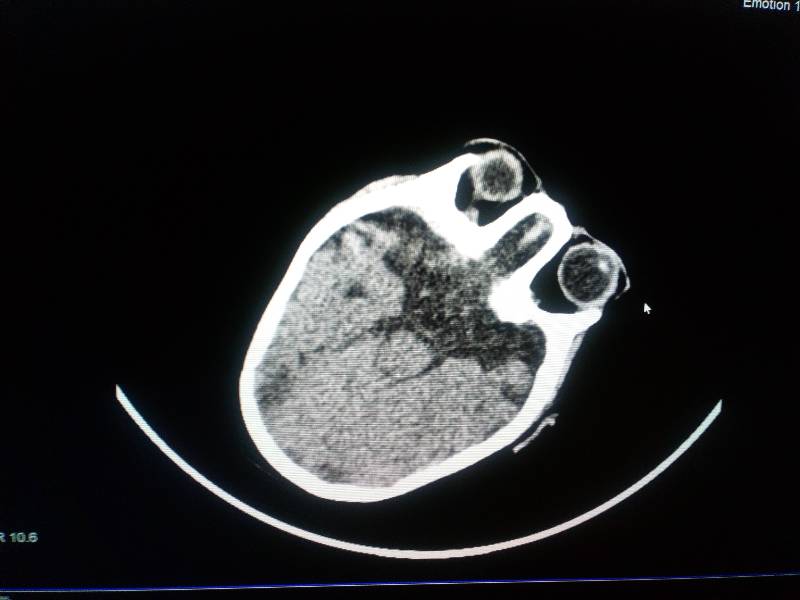

МРТ было сделано в 2009 году.

на фото стоит 16г

@мама лили, я фотала снимок мрт на телефон, там автоматом ставится дата. А само МРТ 2009 года.

У меня лобарная голопрозэнцефалия (это по поводу МПЩ). Гипоплазия мозолистого тела. Данные диагнозы по МРТ поставить было невозможно, только после того как я череп залезли эндоскопом и все увидели.

на снимке мпщ есть, я вам ее выделила. а то, что она с дефектом частичного срастания - это дело 5ое.

мама лили, посмотрите наше мрт, вся запись на диске, выбрала несколько фото

почему то одно только загрузилось